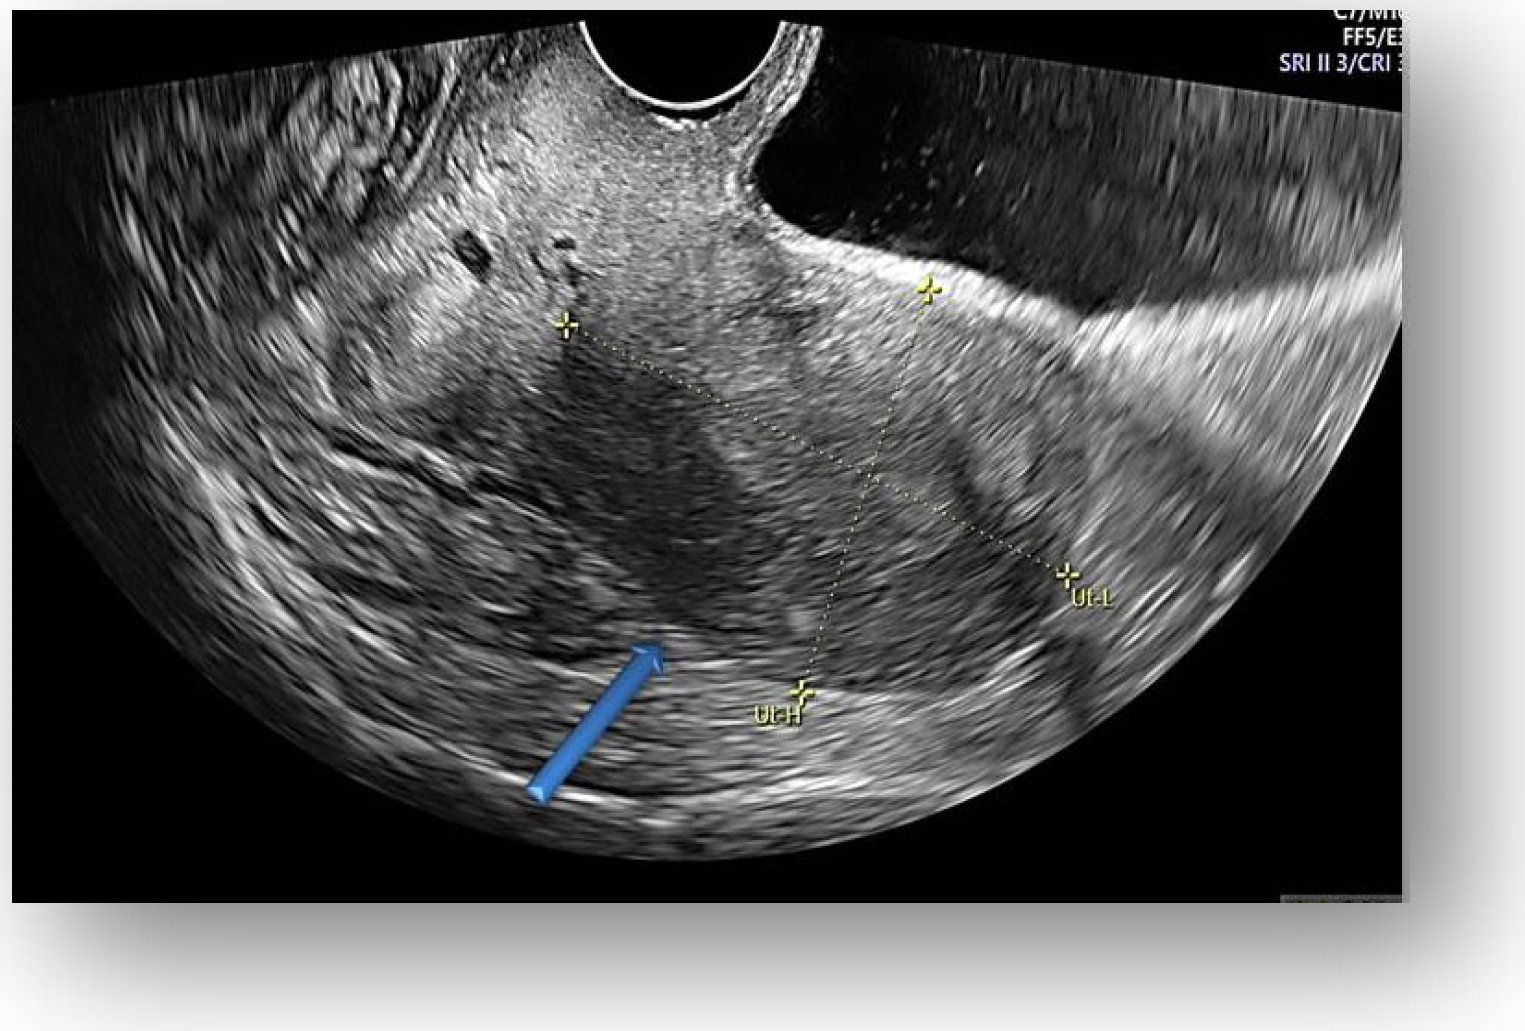

Considering all the information gathered, we first decided to perform an ultrasound (US) which revealed a large hypoechoic cystic formation on the left of the uterus, misdiagnosed as a paraovarian cyst measuring 80 mm (Figure 1, Figure 2, Figure 3 and Figure 4).

Figure 1.

Large hypoechoic cystic formation located to the left of the uterus measuring 80 mm.

Figure 2.

Hypoechoic cystic formation with peripheral doppler flow, without intracystic vegetations.

Transvaginal ultrasound showed uterine body with normal endometrium.